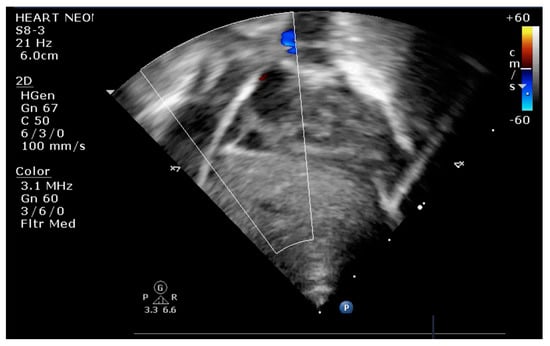

The indication for balloon atrial septostomy was made based on clinical status (low systemic arterial oxygen saturation) correlated with tissue hypoxia (persistently elevated lactate level), echocardiographic assessment (patency and size of interatrial septal defect, ductus arteriosus, and interventricular septal defect), and anticipated delay to surgery. The procedure was performed according to the institutional protocol, at the patient’s bedside, under general anesthesia, and using the Rashkind pull-back technique under echocardiographic guidance (Figure 1 and Figure 2). Vascular access was obtained via a sterile technique via the femoral or umbilical vein. The procedure was repeated several times until satisfactory atrial communication was obtained. The success of BAS was clinically objectified by increasing systemic arterial saturation by at least 10% and echocardiographically objectified by increasing interatrial communication (Figure 3).

Figure 3.

Transthoracic echocardiography subcostal view: large communication at the level of IAS after BAS.